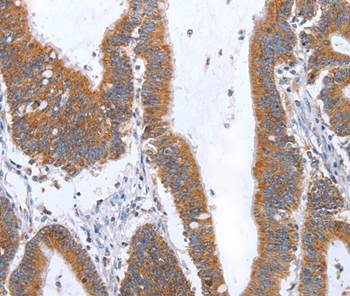

Immunohistochemical analysis of paraffin-embedded Human colon cancer tissue using #35963 at dilution 1/35.

Immunohistochemical analysis of paraffin-embedded Human esophagus cancer tissue using #35963 at dilution 1/35.